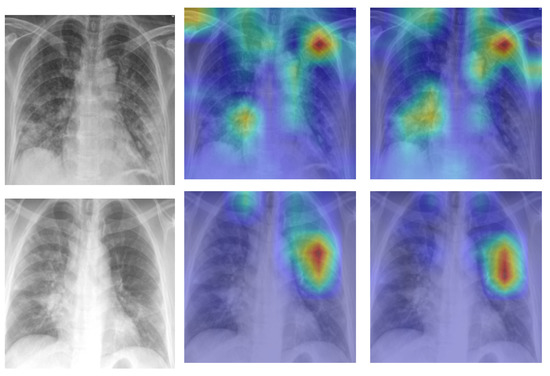

8. Model Explainability

A Self-Attention with MLP module and a Standard Transformer Encoder make up the visual transformer. We visualised the signs recognized by ViT using the attention map of ViT-B32 in order to better understand how the model learned to recognize the COVID-19 signs. The self-attention score for the model can be used to visualize the input image. In this investigation, the jet colour scheme is employed. The blue tones in this colour scheme indicate lower values, which indicate that no features are extracted for a particular class, while the yellow and green tones indicate medium values, which demonstrate an intermediate probability for being in a particular class; the red and dark red tones indicate higher values, which indicate that the features in the region correspond to the particular class. Figure 9a shows samples of true positives with the attention map. The images demonstrate that the affected area was highlighted more precisely by the P2PFL than by non-P2PFL model. This shows that after the model aggregation of the two hospitals, we obtain a robust model to detect signs of COVID-19. The detection of signs becomes more accurate if high resolution CXR images are used.

Figure 9. Example of explainability COVID-19 cases on hospital-1 and hospital-2 using P2PFL and non-P2PFL: column (a) original images, (b) TP COVID-19 cases for non-P2PFL, (c) TP COVID-19 for P2PFL.